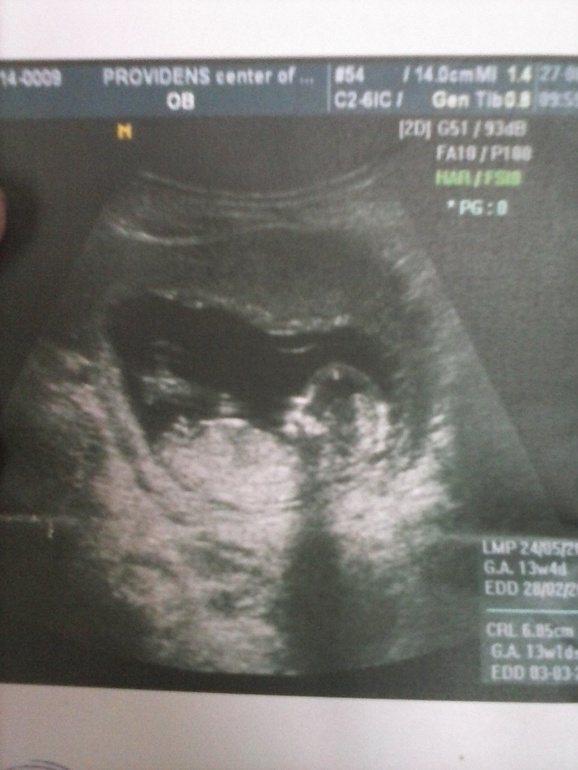

УЗИ, КТГ, доплерПо УЗИ срок 12 недель и 6 дней

вот УЗИ,смотрите как расположен бугорок